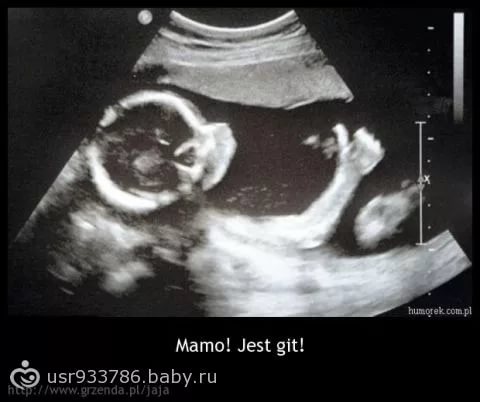

Фотка из Интернета,т.к в жк фото не распечатывают. 1 августа прошла второй скрининг,вся тряслась от переживаний,сердце из груди выпрыгивало,никогда его так громко не слышала) ну зря переживала,с малышом все ок! В какой-то момент узистка сказала:"ой,редкий кадр" и повернула ко мне монитор. А там малыш показывает "Лайк"))) но партизан,снова сдвигает ноги и сидит на попе,пол не видно. Сначала ей что-то там показалось,но потом когда стала смотреть говорит,нет,не могу ничего разглядеть,поэтому пока сюрприз для нас,кто в домике живет. Главное,что здоровый! Уже за вечер и на сына настроилась,вообщем готова к любому полу, только бы поскорее, чтобы начать покупать одежку. С мужем хочу пойти на платное узи, чтобы сделать фоточки и наконец-то выяснить Лёха или Катюша. Малыш сейчас на 20 недель и 2 дня. Вес 341 г, сердцебиение 151, окружность головы 177, живота 149. Плацента по передней стенке, на 45 мм выше зева.